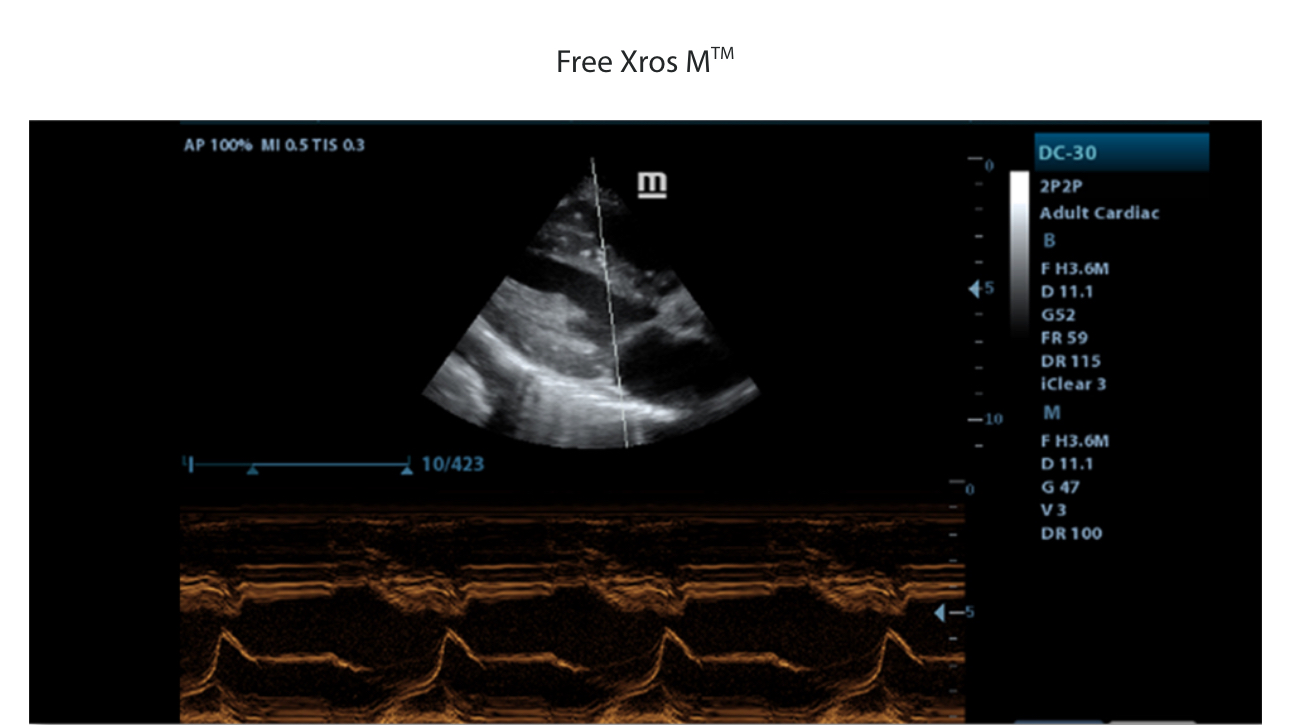

- Free Xros M, Gain precise anatomical observation by freely placing sample lines at any angle.

| Cardiac Functions | ECG module, Free Xros M, Tissue Doppler Imaging (TDI) |